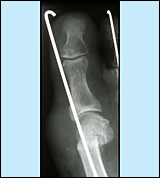

Subcapitale Verschiebeosteotomie nach Kramer/Bösch

- Korrektur der Lage des Mittelfußköpfchens

mit Durchtrennung des Knochens und einfache Stabilisierung

mit einem kräftigen Draht. Dieser wird nach ca. 4 Wochen

ohne weiteren Eingriff von außen entfernt.

- Vorteil: kleiner Hautschnitt, geringe

Schwellung, keine weitere Operation, sichere Stabilisierung

- Bei milden Fehlstellungen und frühen

Stadien des Ballenzehs